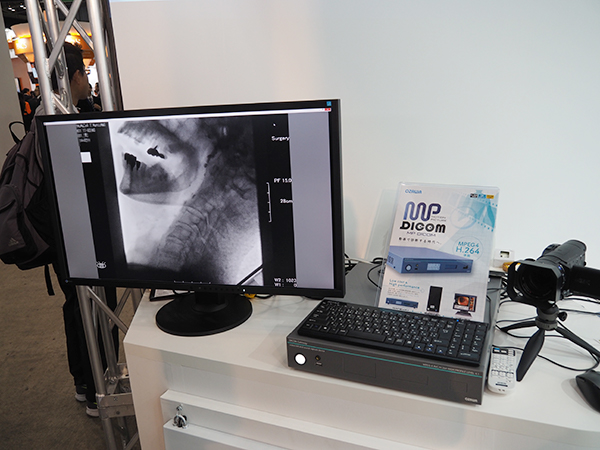

●MPEG4/H.264に対応したDICOM動画像システム「MP DICOM」

ONIS 3によって動画像データのDICOMでの取り込みを可能にする「MP DICOM」を今年も展示した。循環器や内視鏡などの動画像をDICOMデータとして取り込み,保存,参照が可能で,小沢医科器械(岡山県倉敷市)が販売する。DICOM非対応の装置の動画をキャプチャーして変換する「MP DICOM GATEWAY」と,ONIS3を搭載した「MP DICOM SERVER」「MP DICOM VIEWER」で構成される。

動画像データのDICOMでの取り込みを可能にする「MP DICOM」